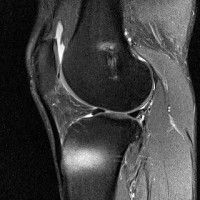

무릎 mri 간단히 봐주실 수 있으시나요 ㅠㅠ

안녕하세요 8년전 십자인대 수술하고 최근 무리한 운동에 무릎 불편감이 생겨서

mri 찍었습니다.

진단결과는 첫 찍은 병원에서 활액막염 이라는 진단을 받았습니다. 혹시 봐주실 수 있으실까요?

올라온 MRI가 단편적이라서 정확한 진단에 어려움이 있지만 십자인대에는 큰 이상이 있지는 않은것 같으며, 무릎관절내 물이 있는 것으로 보아 활액막염의 진단이 맞을 것 같습니다.

하지만 단편적인 영상이기 때문에 촬영병원에서 정확한 판독지 등을 받으시는 것이 좋겠습니다.